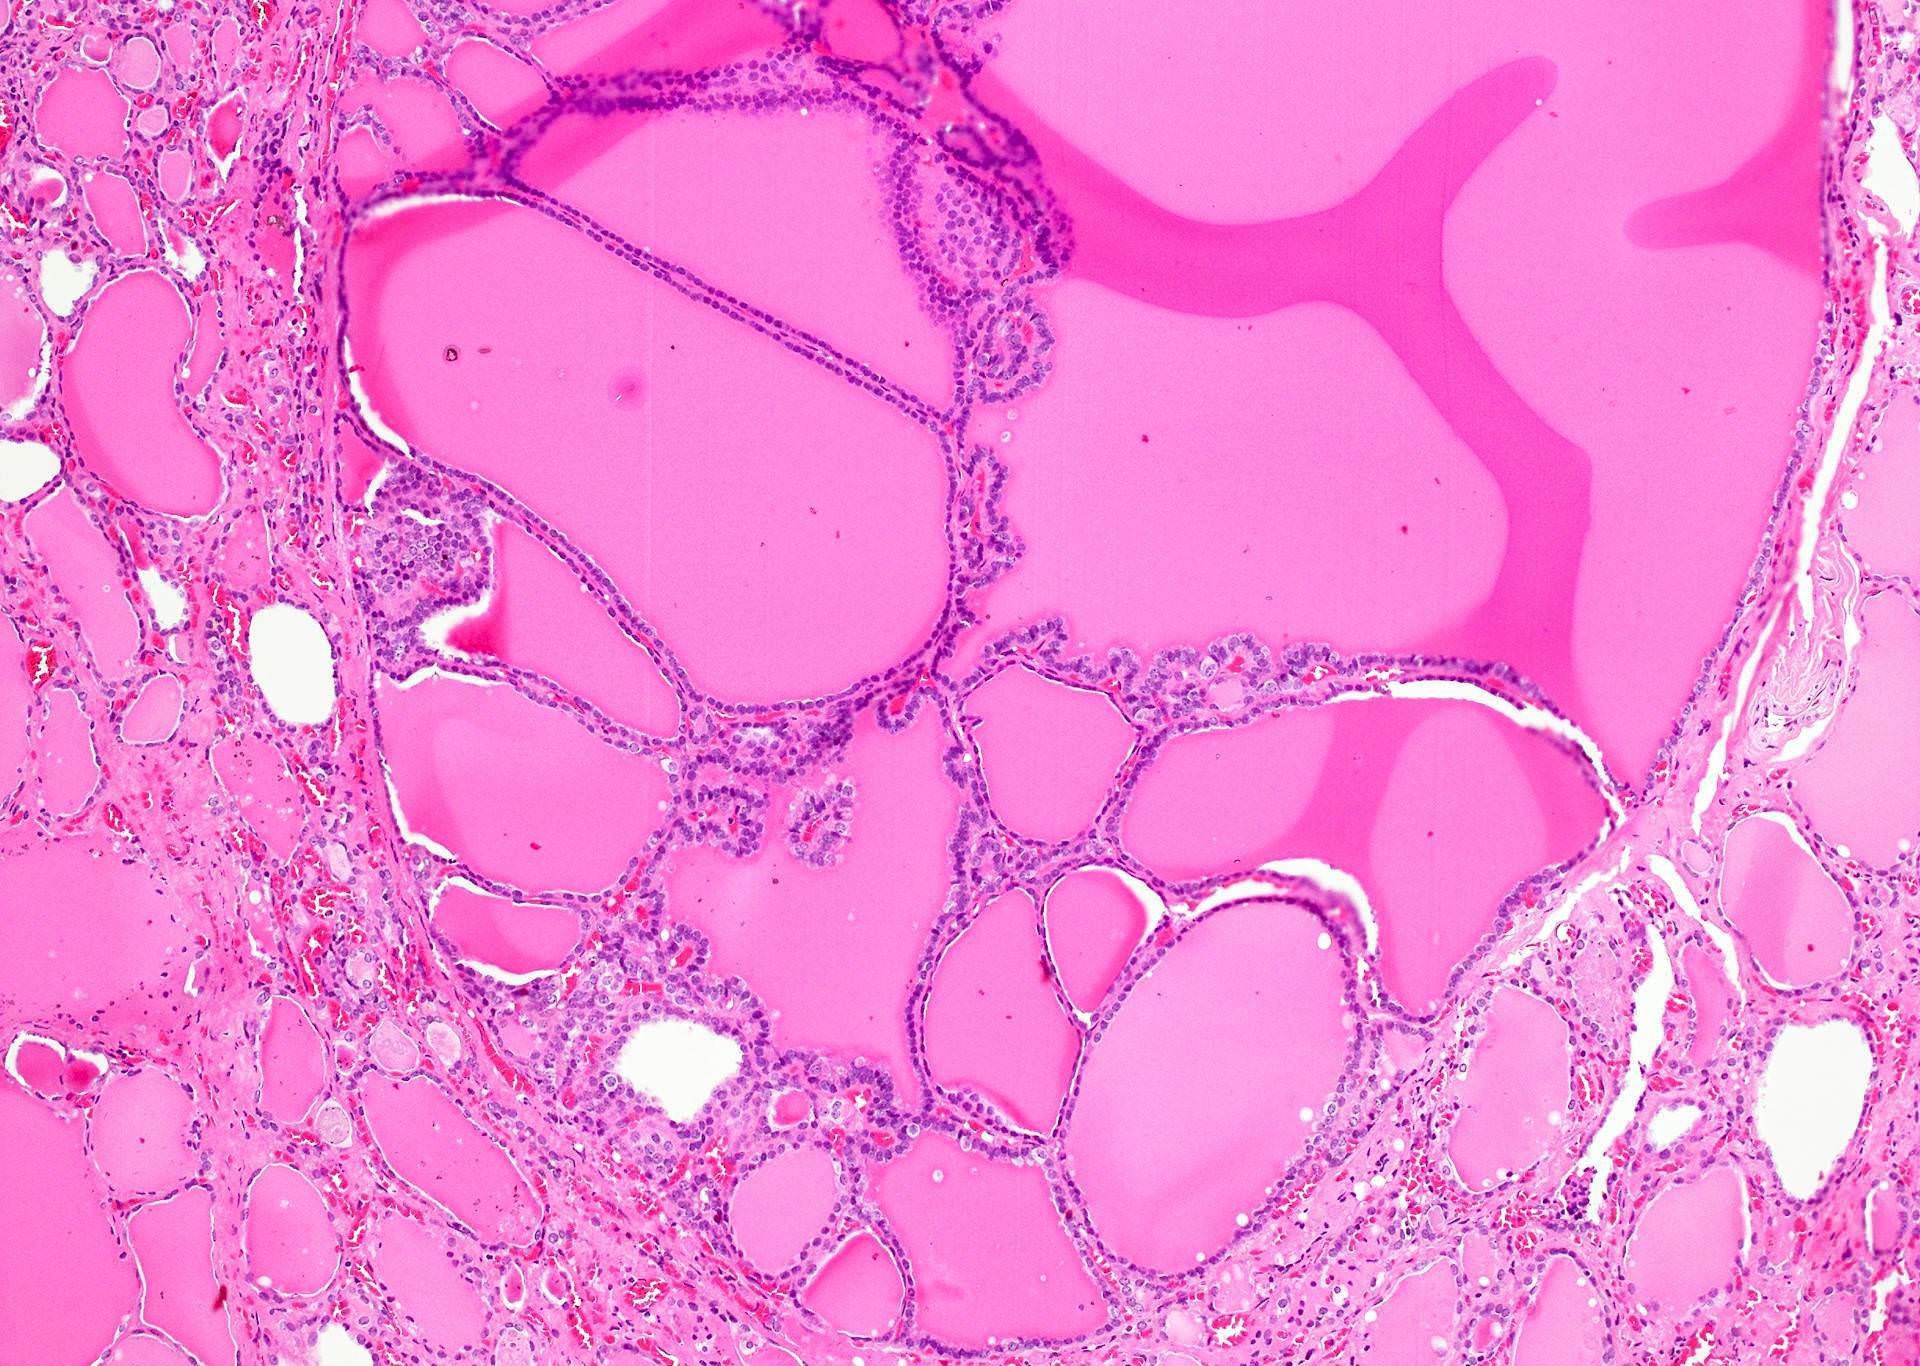

Microscopic (histologic) description

- Variable sized dilated follicles with flattened to hyperplastic epithelium

- Nodules with variable histological patterns: from colloid and microfollicular to hypercellular / microfollicular

- Secondary changes may be seen, including foci of fresh or old hemorrhage, rupture of follicles with granulomatous response, fibrosis, calcification and even osseous metaplasia

- Some of the cystically dilated follicles may show papillary projections (Sanderson polsters) that may mimic papillary carcinoma; however, they lack the nuclear features of papillary carcinoma

Microscopic (histologic) images

Contributed by Swati Satturwar, M.D., Andrey Bychkov, M.D., Ph.D. and Rajeshwari K. Muthusamy, M.D.

AFIP images

C. Variably sized follicles with flattened hyperplastic epithelium, cysts, hemorrhage, granulomatous response, fibrosis, calcification or osseous metaplasia. Nodules may or may not be present in nodular goiter but generally lack a thick capsule. Prominent features are variably sized dilated follicles with flattened hyperplastic epithelium. Secondary changes include foci of fresh or old hemorrhage, rupture of follicles with granulomatous response, fibrosis, calcification and even osseous metaplasia. Some of the cystically dilated follicles may show papillary projections (Sanderson polsters). Cytologic atypia in the form of highly atypical nuclei occurs in patients exposed to radioactive substances.